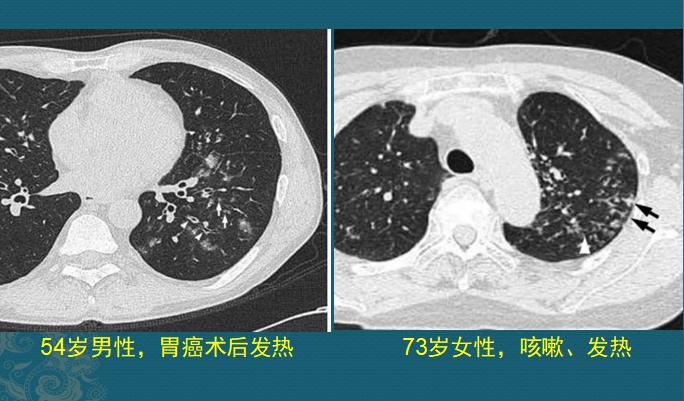

如果它们抵达肺部小血管周围生根发芽,就会制造各种毒素引发炎症,表现为多发点片状影或类圆形结节影,边缘清晰或模糊,沿支气管血管束或肺外周和基底部分布,因为是化脓性感染,多数结节最后会坏死、液化,形成空洞,当损伤血管或者形成血管内菌栓堵塞还可以引起远侧肺组织缺血坏死(肺梗死),形成胸膜下楔形肺实变影。

血源性金葡菌肺炎

这些都是金葡菌小草刚发芽,多发小结节、小斑片影,有的形成了小空洞和小气囊,部分与血管关系密切,提示病菌是从血道来源引起肺部播散,及时抗生素治疗可以压制炎症发展。